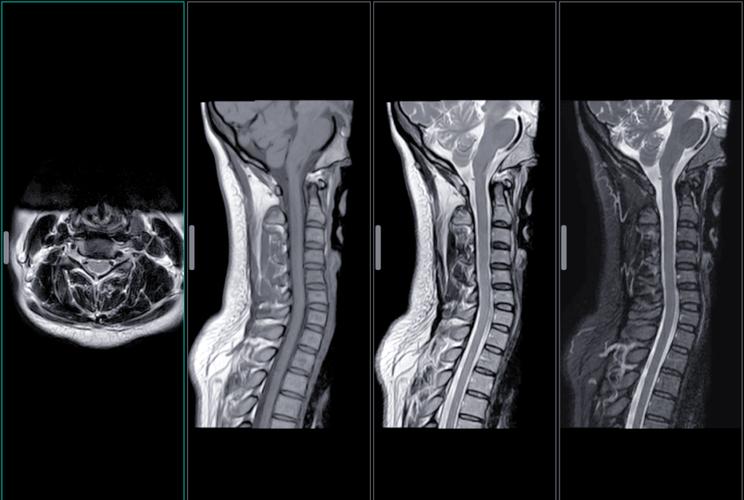

MRI,也就是核磁共振造影,它之所以能夠「看」到我們身體裡清晰的影像,主要是利用了人體內水分子的特性,在高強度的磁場和無線電波的刺激下,產生訊號,再由電腦將這些訊號轉換成影像。在這個過程中,**強大的磁場主要作用在人體的水分子上,並不會直接對腎臟細胞或組織產生破壞性的影響。** 想像一下,它比較像是用一種很精密的「雷達」在掃描,而不是用「刀槍」在切割。因此,單純的MRI掃描,對於沒有特殊情況的健康人來說,對腎臟的負擔幾乎是零。2

在進行MRI檢查時,為了讓某些組織、血管或病灶更加清晰可見,醫生常常會注射一種稱為「顯影劑」的藥物。而大多數時候,大家所擔心的「MRI傷腎」,其實真正要關注的是**「含釓顯影劑」**的潛在風險。3